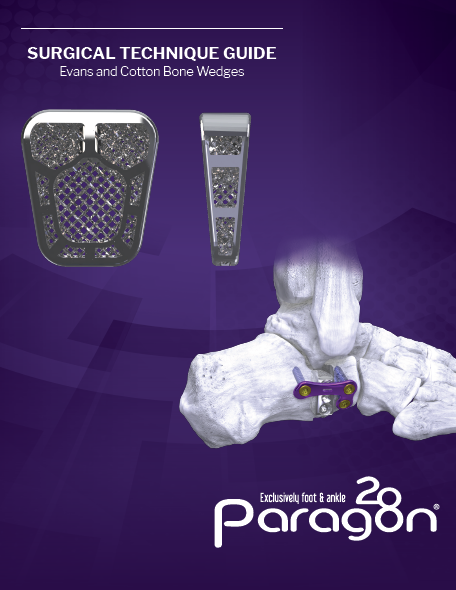

Wedge SystemsADDITIVE ORTHOPAEDICS® Cotton Plantarflexing Osteotomy Wedge

ADDITIVE ORTHOPAEDICS® Cotton Plantarflexing Osteotomy Wedge

A Unique Implant Solution made possible through the use of Additive Manufacturing

Built with LatTi-Structure®

3D printed Ti6Al4V Titanium ELI

Available in 4.5, 5.5, and 6.5mm size options

ADDITIVE ORTHOPAEDICS® Cotton Plantarflexing Osteotomy Wedge

Built with LatTi-Structure®

3D printed Ti6Al4V Titanium ELI

Available in 4.5, 5.5, and 6.5mm size options

PRODUCT DESCRIPTION

The ADDITIVE ORTHOPAEDICS® Bone Wedge System offers a porous titanium wedge that provides an alternative to allograft/autograft bone for a Cotton Osteotomy for plantarflexion of the first ray. The system includes procedure specific shaped Ti6AI4V Titanium ELI wedges in nine sizes. The wedges are additively manufactured and feature a propriety 79% porous lattice structure.